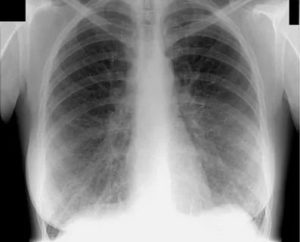

- Рентгеноскопия – осмотр легких в «режиме реального времени». Зону исследования просвечивают рентгеновским аппаратом, и изображение отражается на экране. Рентгеноскопия показывает структуру органа, его изменения, воспалительные процессы, проходимость контрастного вещества (если оно используется) и т.д. Хрипы, грудной кашель, негативные результаты лабораторных исследований являются показаниями к рентгеноскопии. Достоинством метода является его оперативность. С появлением цифровых аппаратов возникла возможность сохранить изображение и распечатать его на бумаге, а лучевая нагрузка снизилась. При рентгеноскопии, как и при всех иных методах рентгенологической диагностики, организм все же получает незначительное облучение, поэтому процедура противопоказана беременным. Специальная подготовка не требуется.

- Рентгенография – метод, схожий с рентгеноскопией. Отличие состоит в том, что изображение органов дыхания проецируется на пленку. Заключение может быть составлено, как только появятся снимки. В зависимости от клиники на его составление уходит от 30-40 минут до 2 дней.

- Флюорография – рентгенологический метод исследования органов грудной клетки, применяемый для скрининга новообразований легких и туберкулеза. Сейчас пленочная флюорография заменяется цифровой, что позволяет сохранить изображение в электронной форме. В профилактических целях рекомендуется делать флюорографию один раз в год. Абсолютных противопоказаний не существует, специальной подготовки не требуется.